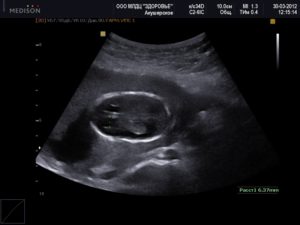

Если на сроке 30 – 32 недели амниотической жидкости меньше чем 1000 мл, то речь идет о маловодии. В зависимости от количества недостачи жидкости в плаценте, диагностируется выраженное или умеренное маловодие при беременности. Для диагностики чаще всего используется УЗИ.

С целью опровергнуть или, наоборот, подтвердить этот диагноз, необходимо провести УЗИ, на основании чего и ставить диагноз. Ультразвуковое исследование позволит точно определить количество жидкости внутри плаценты, а также при подтверждении диагноза, врач с помощью УЗИ оценит степень тяжести и состояние плода. При подозрении на наличие маловодия, беременной стоит пройти осмотр у гинеколога.

При ультразвуковом исследовании врач производит некоторые замеры и расчеты для определения количества околоплодных вод, после чего делает заключение о маловодии, нормальном количестве вод или о многоводии.

маловодие на 18 неделе нужно измерить карманы амниотической жидкости и оценить общее количество вод. Ультразвук может также показывать роста плода, структуру почек и мочевыводящих путей, а также обнаруживать мочу в мочевом пузыре плода.